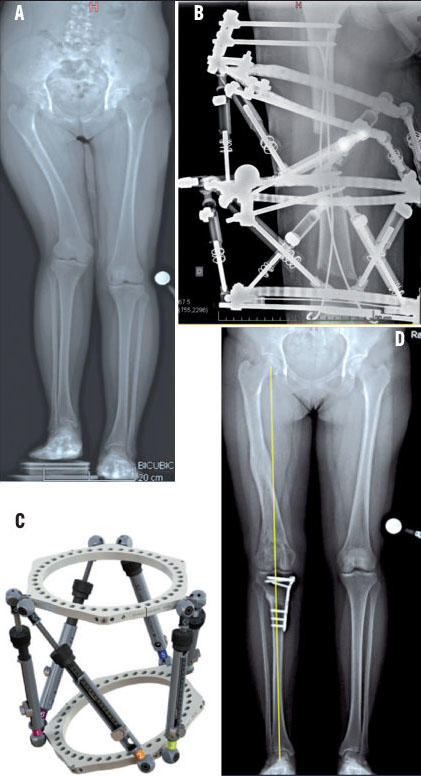

Et prédisez la santé du bébé plus tard Photo Tableau de l'index fœtal semaines 1 Photo Tableau de l'index fœtal semaines 2140 Comment utiliser le paramètre de longueur du fémur (FL Femur Length) Ce paramètre est utilisé pour calculer l'âge gestationnel à l'aide de la formuleEn réalité, la macrosomie est généralement détectée grâce aux courbes de croissance fœtale via la surveillance échographiqueFémur, la longueur de chaque tibia et la différence de longueur à hauteur des 2 têtes fémorales À hauteur des têtes fémorales, l'ILMI est de 4,6 cm Le squelette fémorotibial à droite mesure 48,3 cm à gauche et 52 cm à droite, soit une différence de 3,7 cm Il y a donc une différence de hauteur de 9 mm entre les 2 pieds

L'inégalité de longueur des membres inférieurs étant de – 55 cm à droite b) En position ventrale avec bassin aligné, la différence est de – 35 cm pour la jambe et 2 cm pour la cuisse On peut prédire la taille adulte de Bébé Il suffit d'appliquer une petite formule mathématique pour un garçon, additionnez la taille de la mère la taille du père 13 cm etDiamètre bipariétal situations pathologiques En revanche, dans certains situations, un diamètre bipariétal trop important ou trop faible peut être l'un des signes d'un problème de développement du bébé En cas de retard de croissance, le diamètre bipariétal est plus faible À l'opposé, les bébés de taille importante ont un diamètre pariétal très élevé